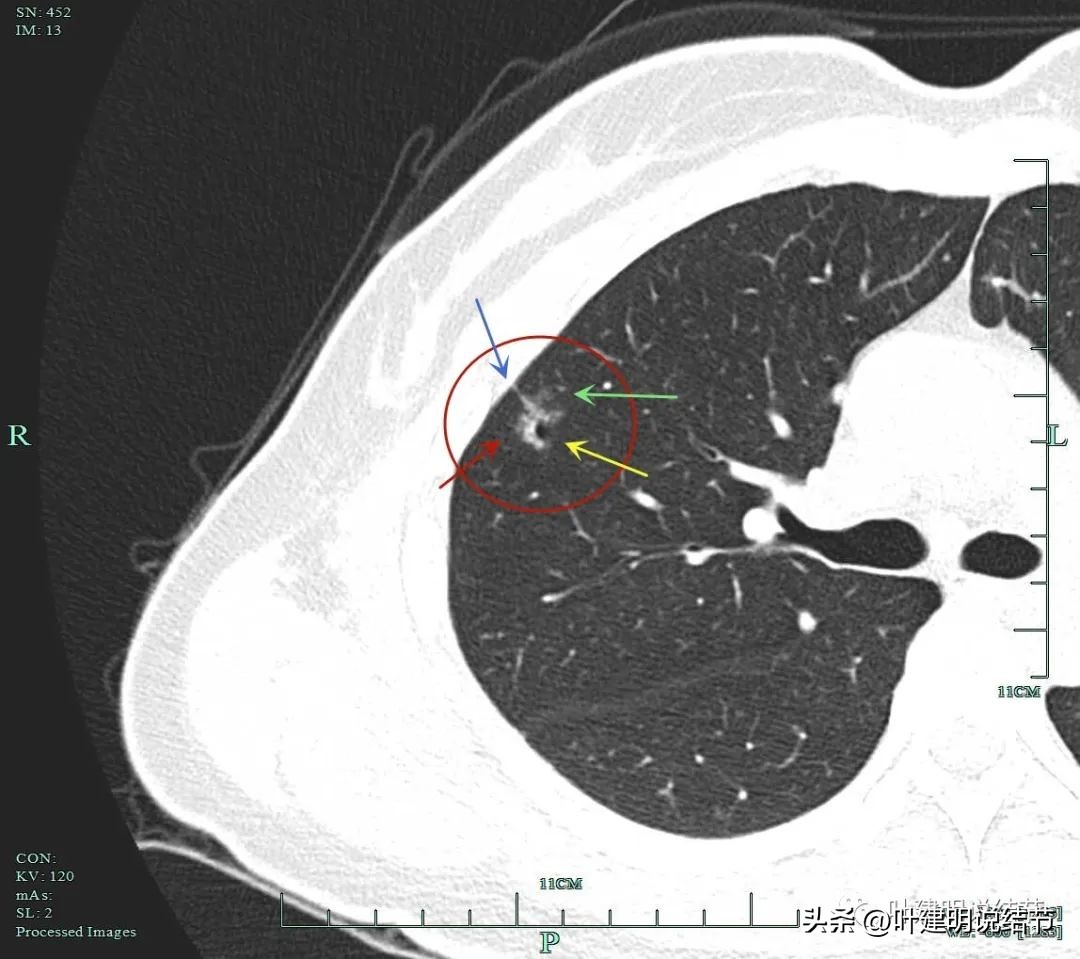

主病灶靶扫描重建影像:

蓝色箭头示月牙铲征;紫色箭头示毛刺或棘突征;桔色箭头示有血管进入并穿行与异常增粗;红色箭头示病灶轮廓与瘤肺边界清楚。

黄色箭头示病灶处有空腔征;粉色箭头示病灶内有实性成分;紫色箭头示毛刺征;绿色箭头示磨玻璃成分轮廓清,有毛刺。

砖色箭头示病灶有分叶征;蓝色箭头示胸膜牵拉;紫色箭头示毛刺征;红色箭头示整体轮廓与瘤肺边界清。总体上看病灶有收缩力、有分叶与毛刺,而且灶内密度不均。是较为典型的浸润性腺癌影像表现。